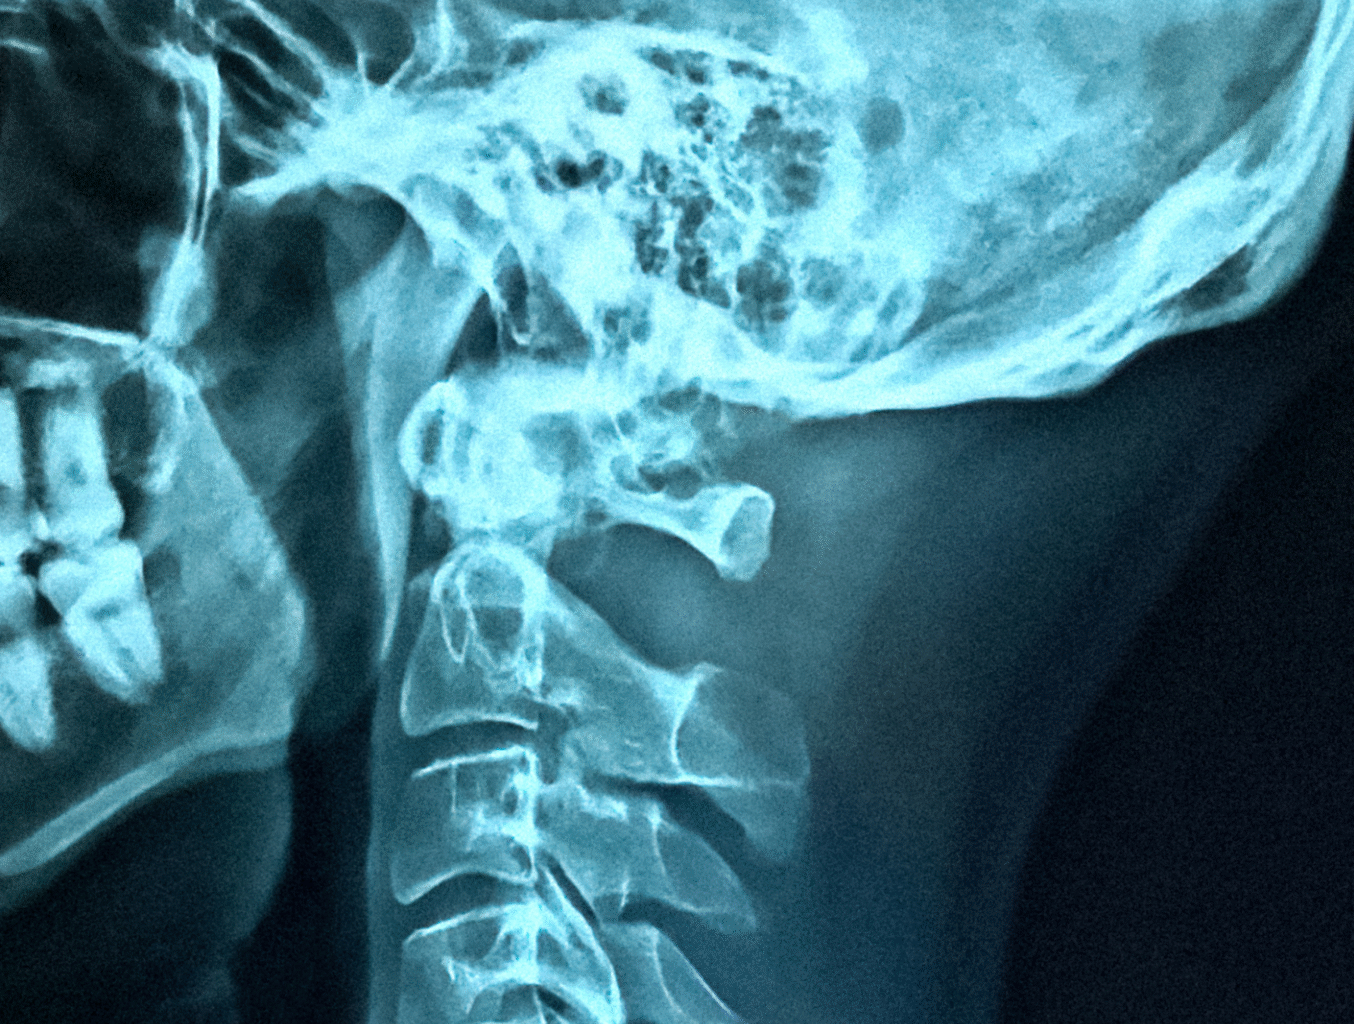

Artificial intelligence (AI) is transforming surgical imaging and with it real-time diagnostics.

Traditionally, surgeons rely on pre-operative scans and visual cues, but AI-assisted imaging reveals details invisible to the human eye, improving identification of critical structures and abnormalities during procedures. This leads to faster, more accurate diagnoses and better-informed treatment decisions. Below, we take a look at some exciting new developments from EnAcuity, Hypervision Surgical, and 3Sonic.

One innovation enabling real-time diagnostics is hyperspectral imaging, which captures more light wavelengths than standard cameras.

Hypervision Surgical, a King’s College London spinout, offers a leap forward. Their system combines a hyperspectral camera with real-time AI analytics to deliver tissue-level insights at over 60 frames per second. It uses safe light and requires no dyes or contrast agents. The AI overlays colour-coded maps of tissue oxygenation onto the surgical view, helping identify poor perfusion or tumour margins. In gastrointestinal surgery, it can highlight ischaemic bowel segments; in oncology, it helps distinguish malignant from healthy tissue. Notably, Hypervision has recently secured UKCA certification in the UK and FDA clearance in the US.

EnAcuity, a spin out company from Imperial College London and UCL, has developed the first hardware-free hyperspectral imaging system for surgery without needing expensive hyperspectral cameras. This highlights tissue perfusions and structures such as vessels, nerves and tumours to the surgeon. The system increases the chance of spotting abnormalities that might be missed by standard vision. For example, subtle differences in blood flow or oxygenation in tissues can signal early-stage disease or compromised tissue. By augmenting the surgeon’s view in real time, EnAcuity’s system supports faster and more accurate intraoperative diagnoses, potentially preventing complications through early detection.